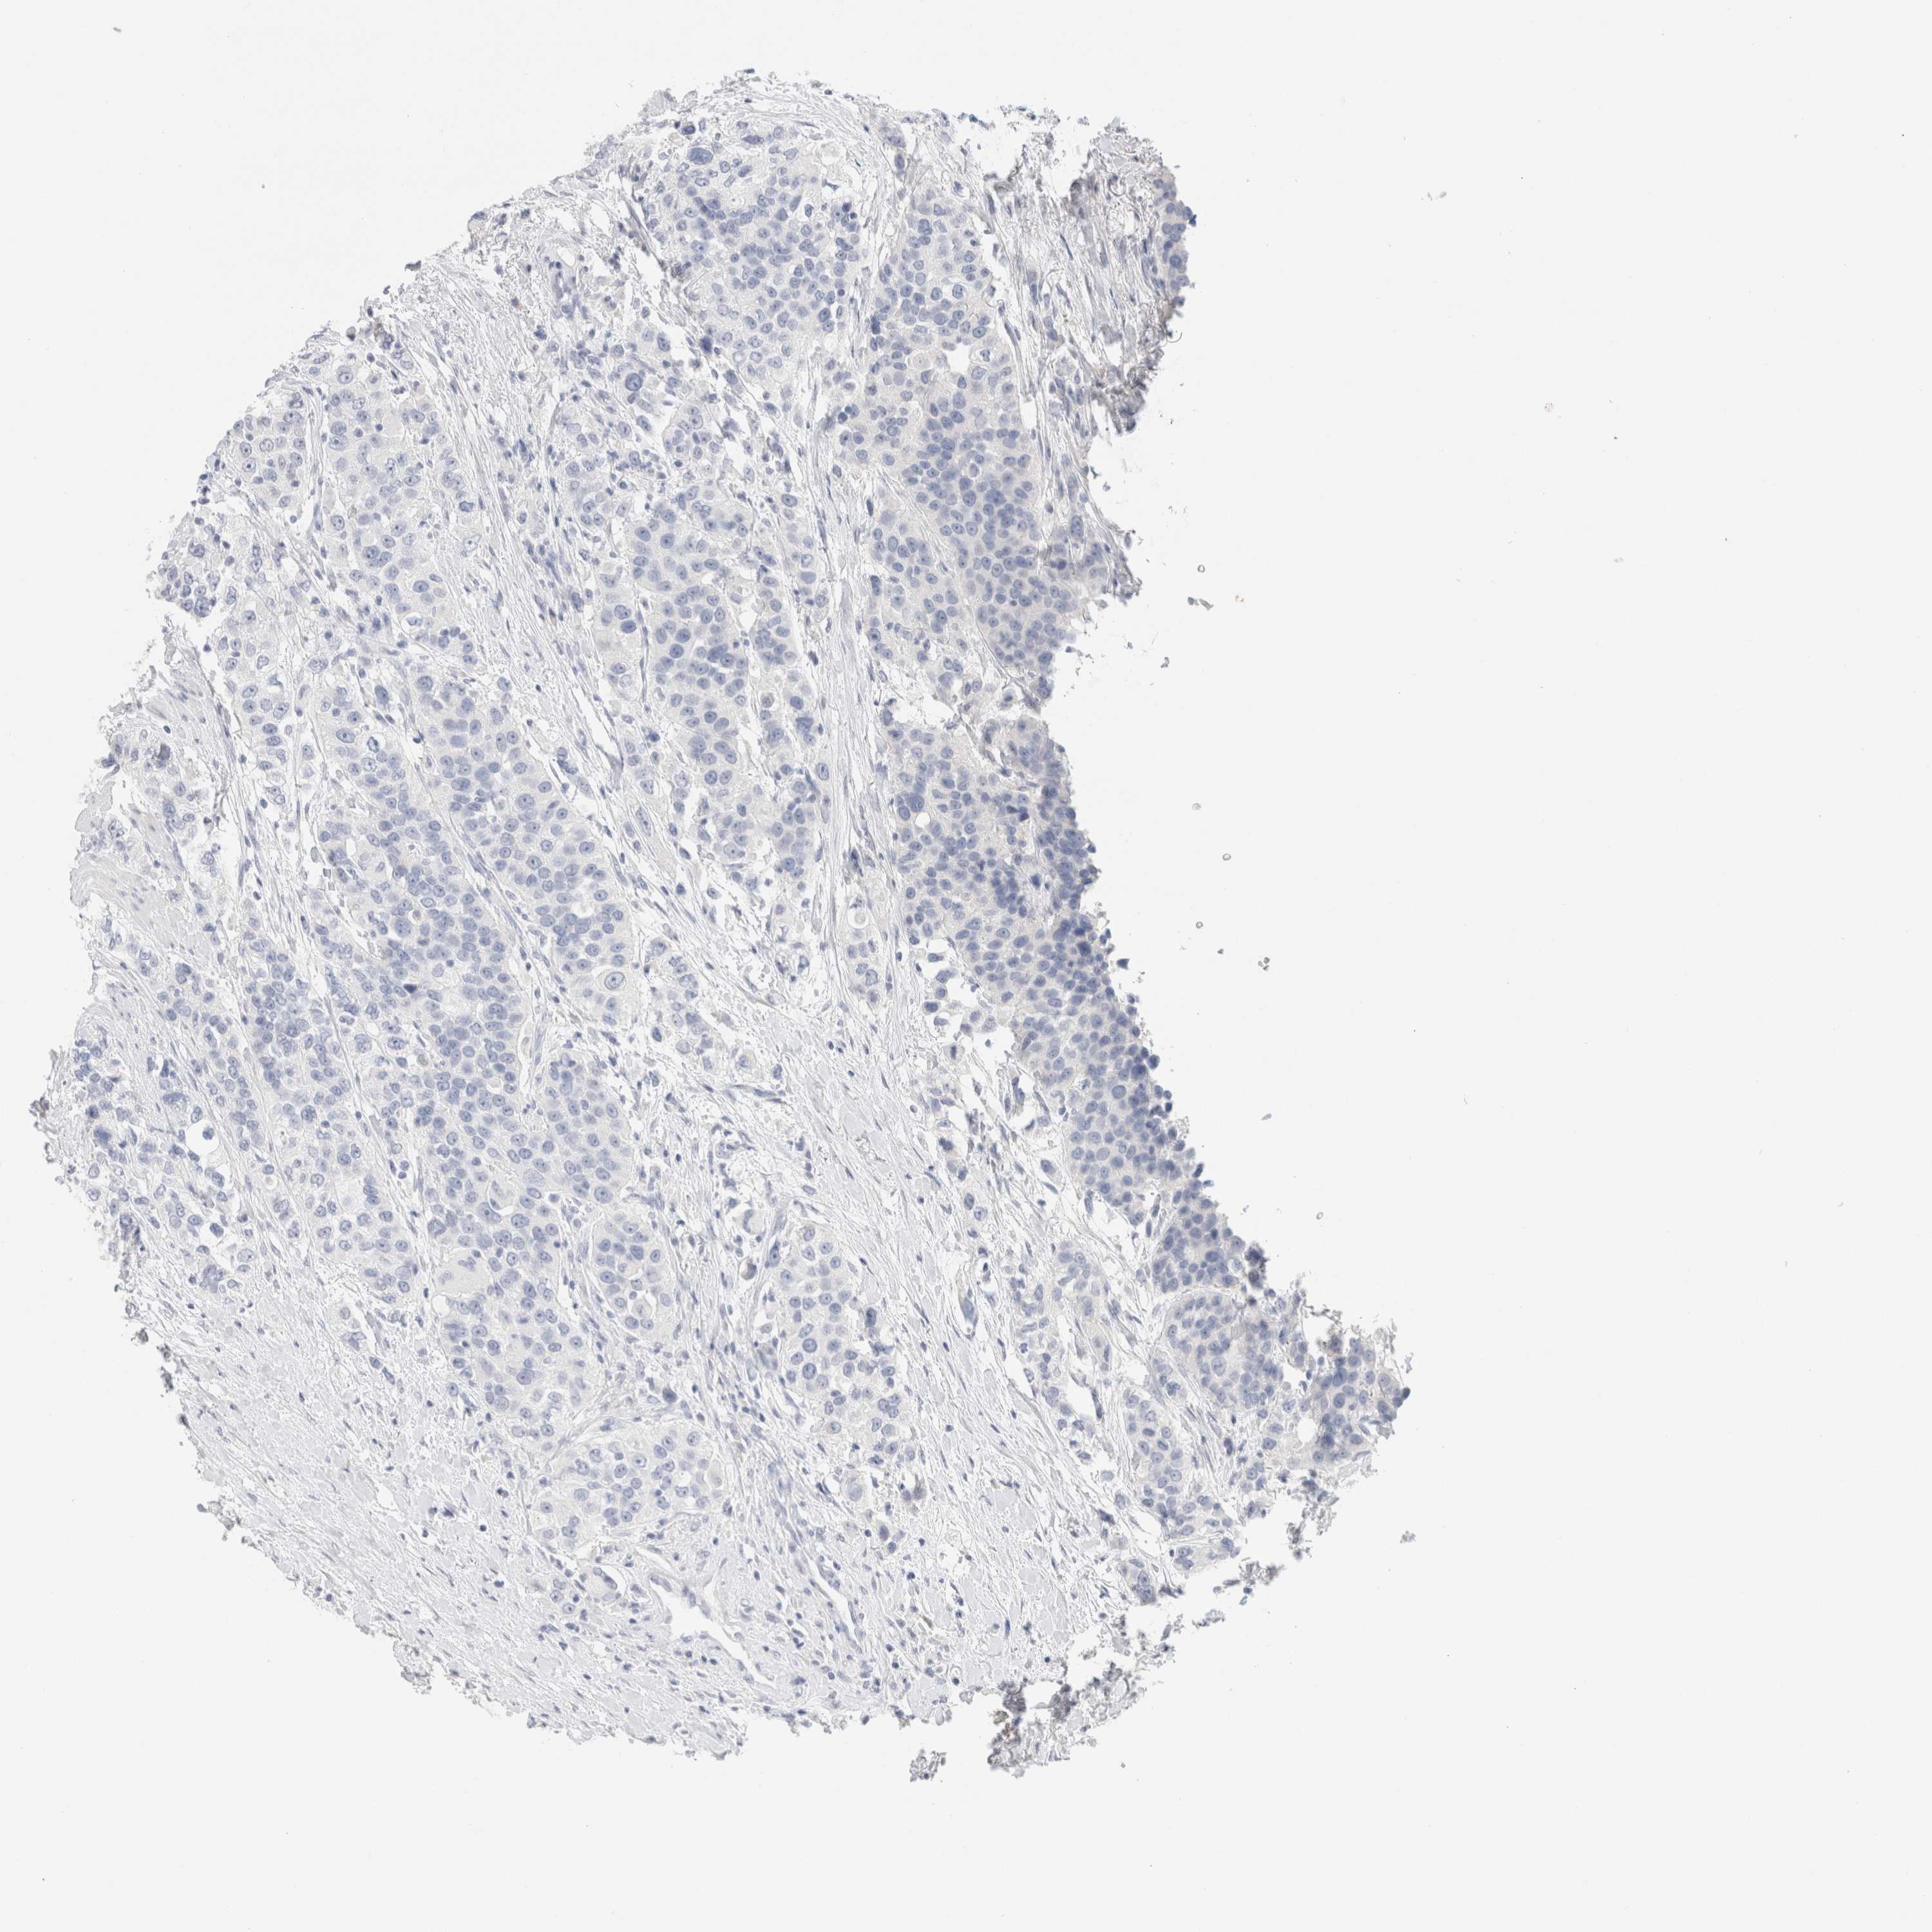

UROTHELIAL CANCER - Protein expressioni

A mouse-over function shows sample information and annotation data. Click on an image to view it in a full screen mode. Samples can be filtered based on level of antibody staining by selecting one or several of the following categories: high, medium, low and not detected. The assay and annotation is described here.

Note that samples used for immunohistochemistry by the Human Protein Atlas do not correspond to samples in the TCGA dataset.

Antibody stainingi

Antibody staining in the annotated cell types in the current human tissue is reported as not detected, low, medium, or high, based on conventional immunohistochemistry profiling in selected tissues. This score is based on the combination of the staining intensity and fraction of stained cells.

Each image is clickable and will lead to virtual microscopy that enables deeper exploration of all samples and also displays staining intensity scores, fraction scores and subcellular localization as well as patient and tissue information for each sample.

Antibody HPA022845

Antibody HPA023138

Antibody CAB010900

Antibody CAB012976

Urothelial carcinoma, Low grade

Urothelial carcinoma, High grade